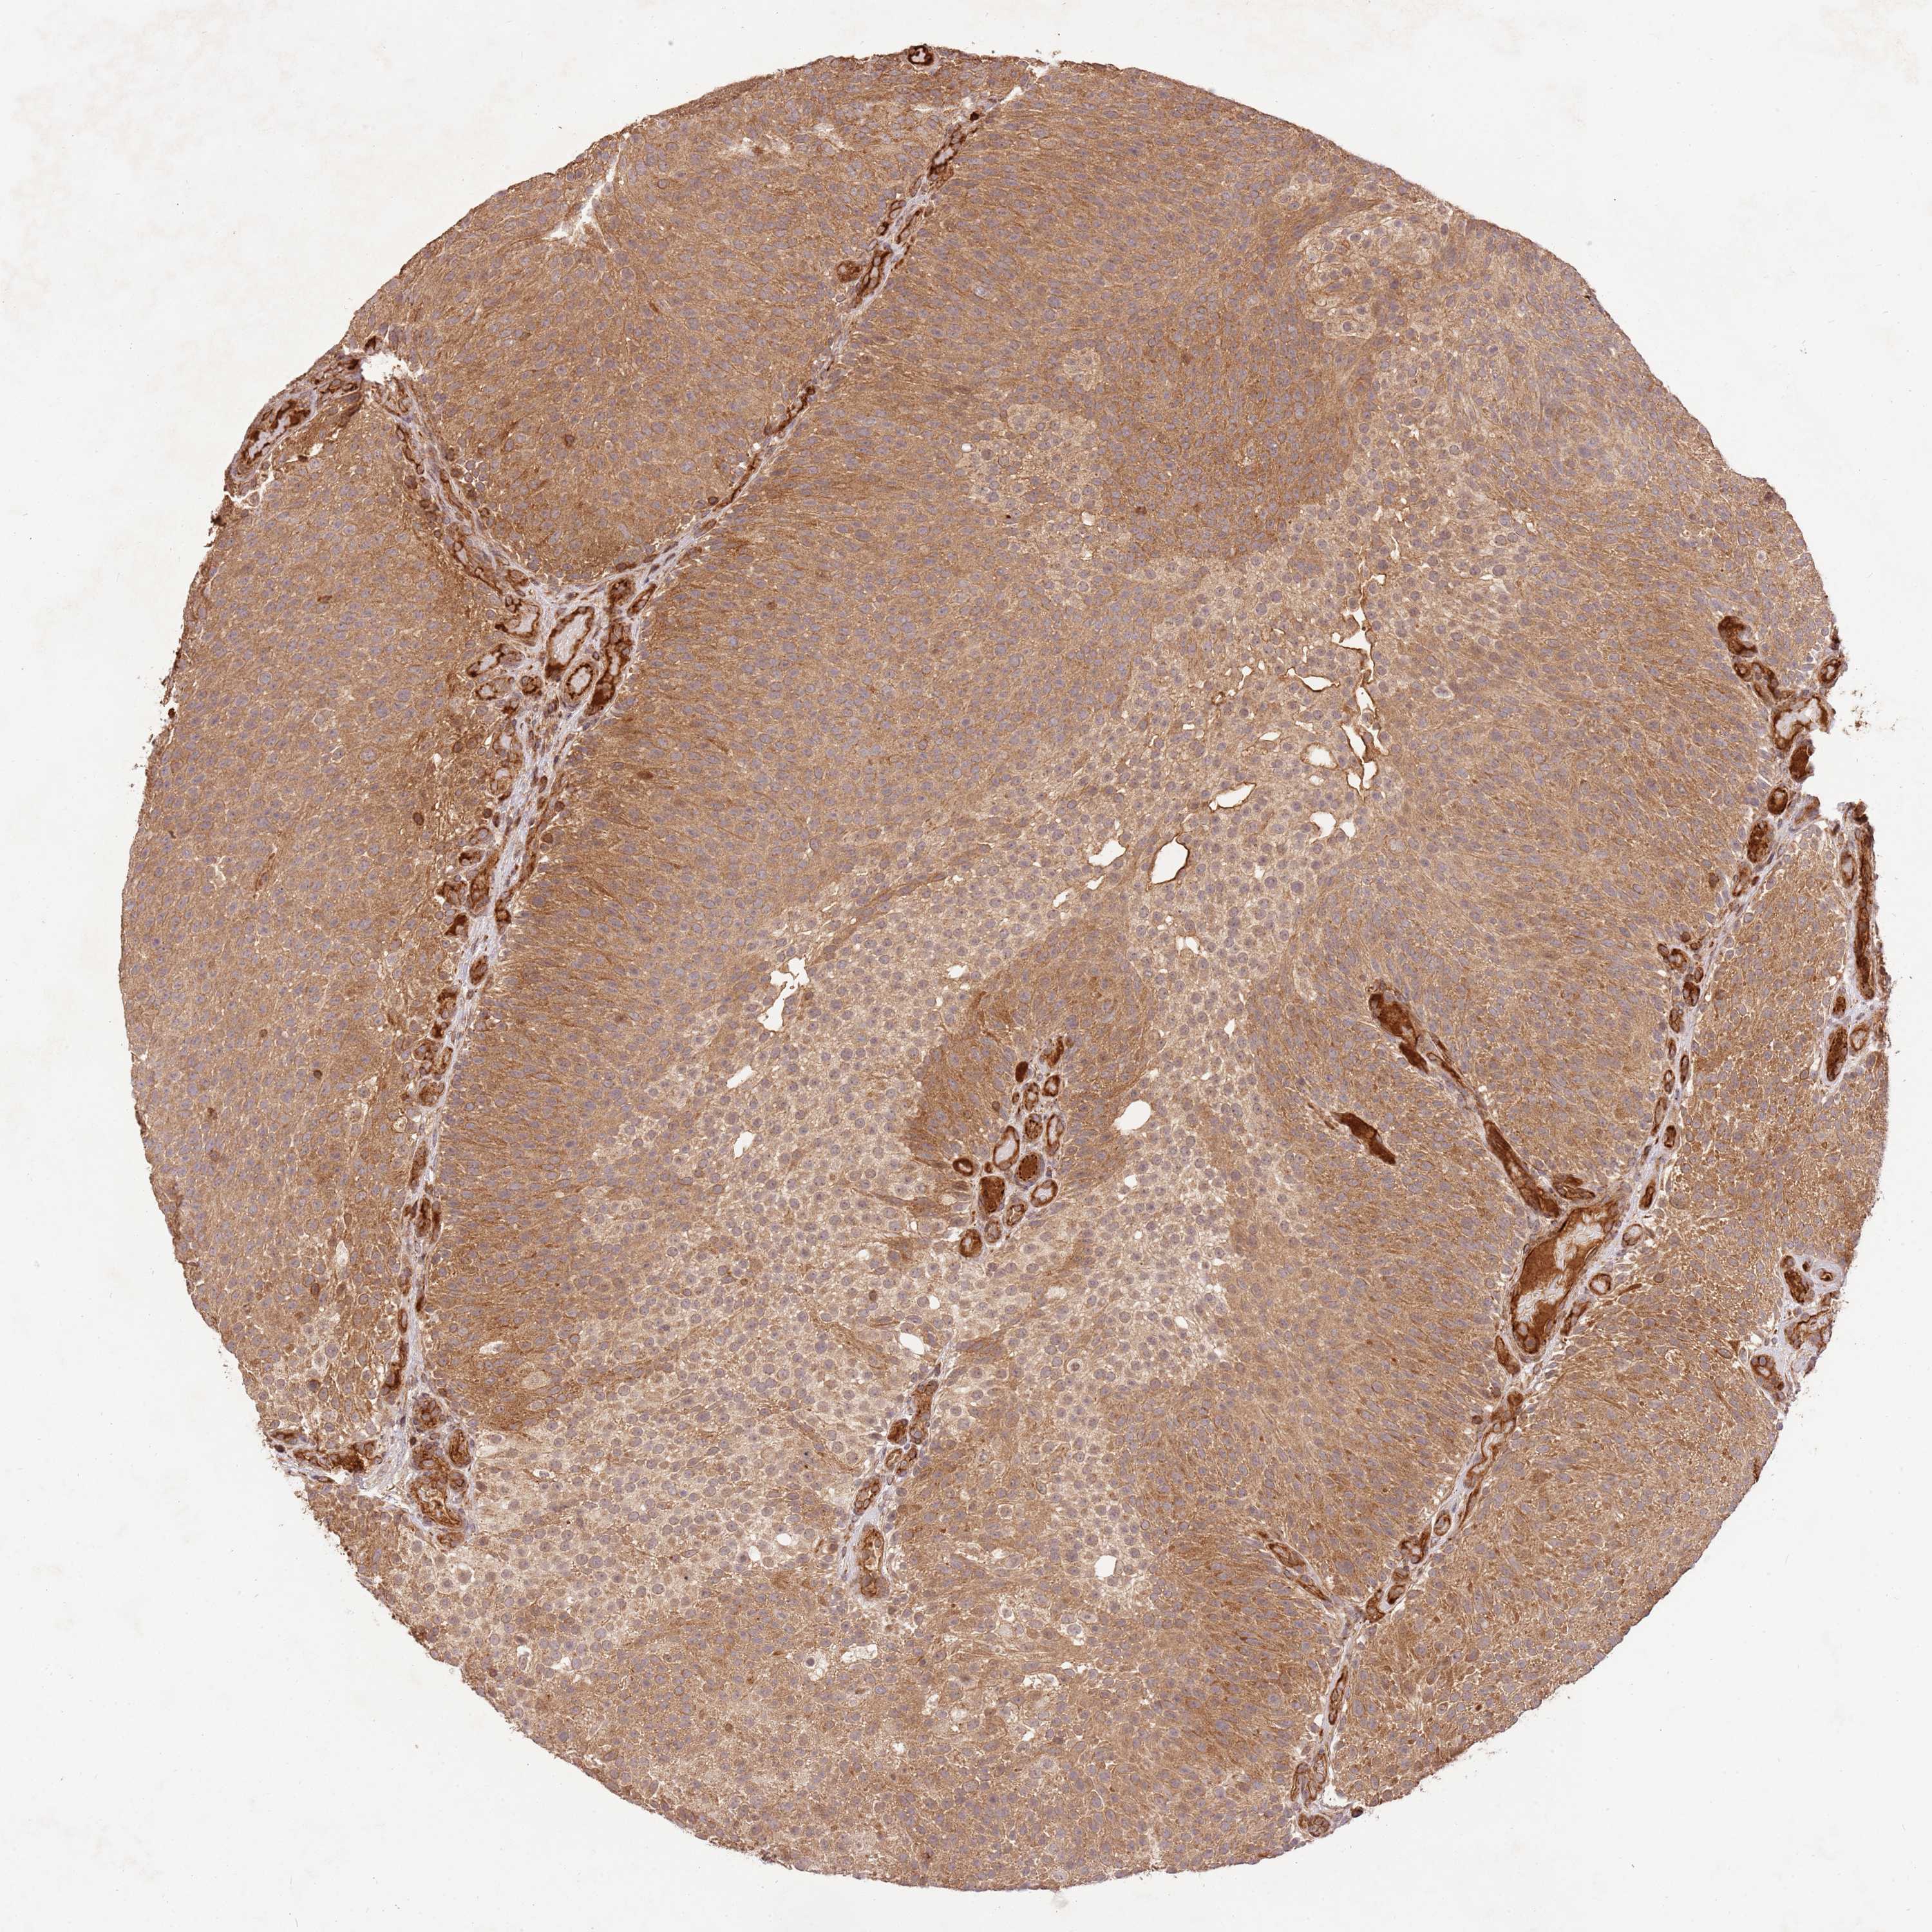

UROTHELIAL CANCER - Protein expressioni

A mouse-over function shows sample information and annotation data. Click on an image to view it in a full screen mode. Samples can be filtered based on level of antibody staining by selecting one or several of the following categories: high, medium, low and not detected. The assay and annotation is described here.

Note that samples used for immunohistochemistry by the Human Protein Atlas do not correspond to samples in the TCGA dataset.

Antibody stainingi

Antibody staining in the annotated cell types in the current human tissue is reported as not detected, low, medium, or high, based on conventional immunohistochemistry profiling in selected tissues. This score is based on the combination of the staining intensity and fraction of stained cells.

Each image is clickable and will lead to virtual microscopy that enables deeper exploration of all samples and also displays staining intensity scores, fraction scores and subcellular localization as well as patient and tissue information for each sample.

Antibody HPA040712

Antibody HPA042029

Urothelial carcinoma, Low grade

Urothelial carcinoma, High grade

Urothelial carcinoma, NOS